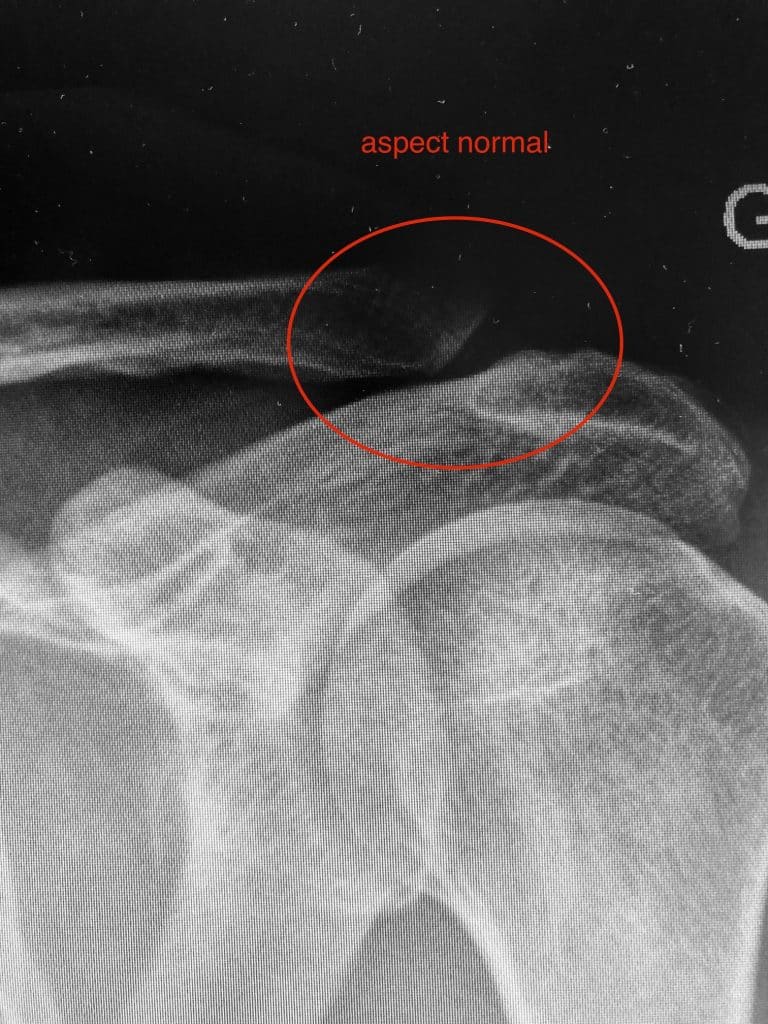

Traumatisme de l’acromio-claviculaire ou disjonction acromio-claviculaire

Suite à une chute sur l’épaule, ce traumatisme engendre soit une simple douleur avec ou sans bosse, soit une véritable luxation acromio-claviculaire avec ascension de la clavicule.

Acromio-claviculaire normale